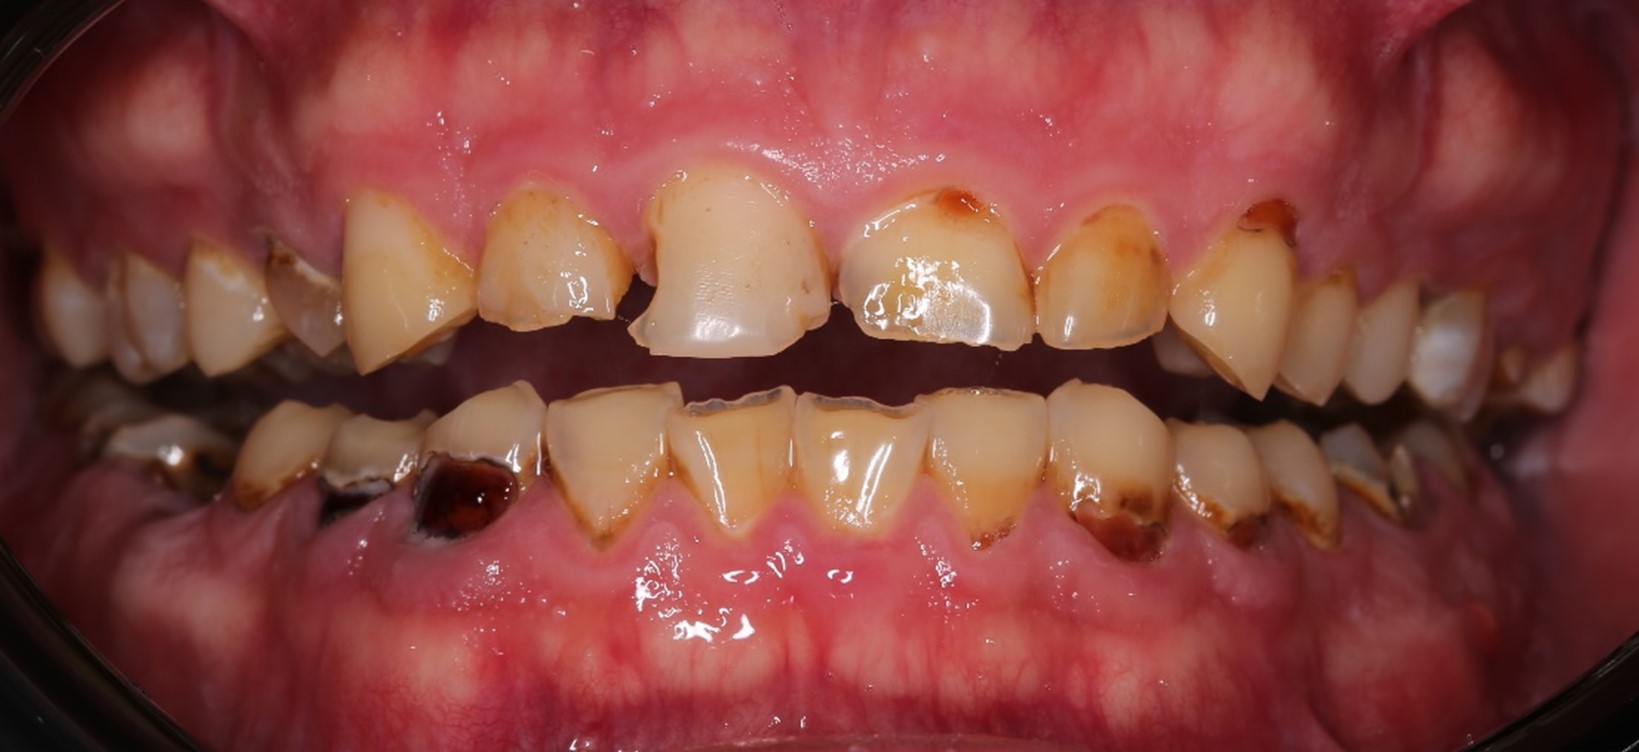

Напоминаю: он пришёл к нам вот в таком состоянии:

На нижней челюсти у него жевательных зубов не было вообще:

Жалобы были не только на внешний вид зубов, но ещё и на проблемы с дыханием и приёмом пищи. Общаться с людьми было тоже некомфортно.

Во-первых, нам нужно было сохранить как можно больше живых зубов при условии, что ни одного целого не было: везде либо вторичный кариес под пломбами, либо сколы, либо стёртые зубы, либо сильно разрушенные. А на фронтальной группе — всё это сразу.

В жевательном отделе зубов практически нет. На зубах с первого по пятый появились небольшие фасетки стираний, которые означают, что прикус зафиксирован именно на них. Если они настолько отчётливые, как у Ивана, это значит, что зубы начинают стираться, и высота нижнего отдела лица уменьшается. Значит, придётся повышать прикус, чтобы вернуть височно-нижнечелюстной сустав и зубы в первоначальную здоровую позицию. Это будет моей задачей.